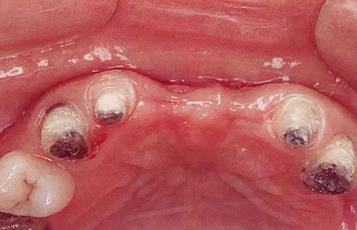

360截圖20170422101910161.jpg

▲圖7-1

對(duì)上頜前牙進(jìn)行初期治療后的咬合面觀。右上2,3存在炎癥。